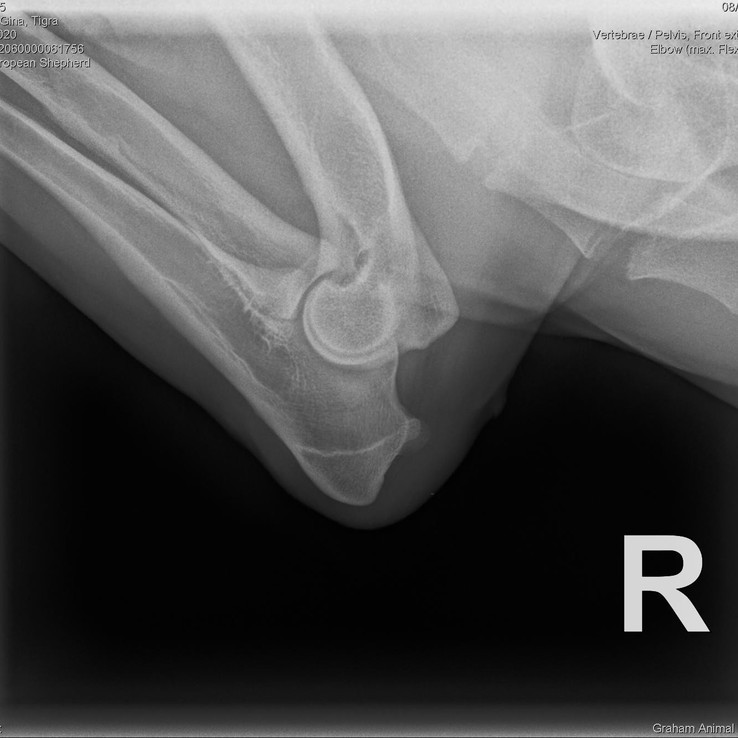

Tigra

Date of Birth: July 10, 2020

Weight: 91 lbs (41 kg)